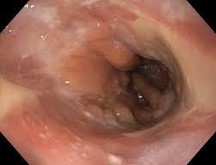

Se decide abordar mediante endoscopia alta y tomografía de abdomen y pelvis encontrando, en endoscopia alta incapacidad para progresar de las 2da porción del duodeno (figura 1) por compresión extrínseca que impide el paso del endoscopio.

Figura 1. Endoscopia alta

Se aborda entre los diagnósticos diferenciales la posibilidad de compresión extrínseca por masa o neoplasia por lo que se decide abordar mediante técnica de imagen para descartar entre los diagnósticos diferenciales los antes mencionados.